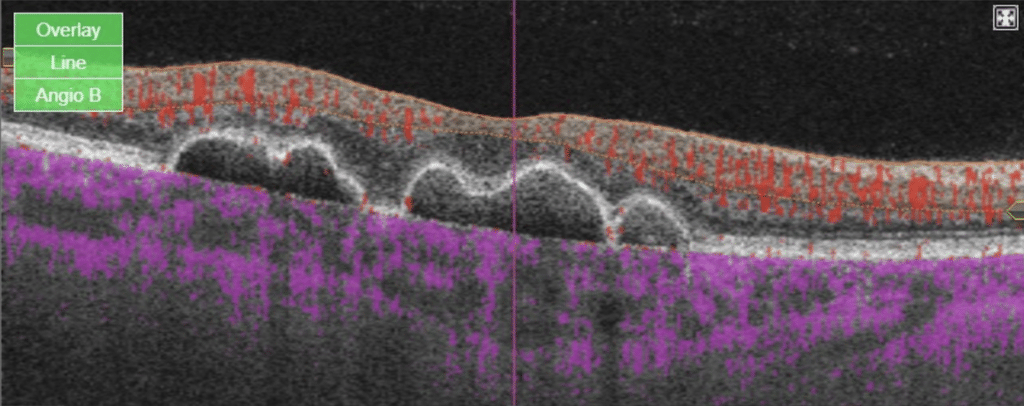

On examination, she had a best corrected visual acuity of 20/20 vision in both eyes. Intraocular pressures were normal and the anterior segment examination was unremarkable. Posterior examination revealed retinal pigment epithelium (RPE) mottling and pigment epithelial detachments (PED) in the macular region as well as nasally in both eyes. Fundus findings were symmetric in both eyes (see Figure A-D). Optos ultra-widefield imaging revealed macular RPE mottling with PEDs in the macula and nasally (see Figure A). Ultra-widefield fundus autofluorescence demonstrated hypoautofluorescent areas with hyperautofluorescent borders in the macula with hyperautoflourescent spots nasally (see Figure B). Macular optical coherence tomography (OCT) scans of both eyes showed PEDs with Bruch’s membrane thickening along with sub-RPE drusen-like deposit (see Figure C).